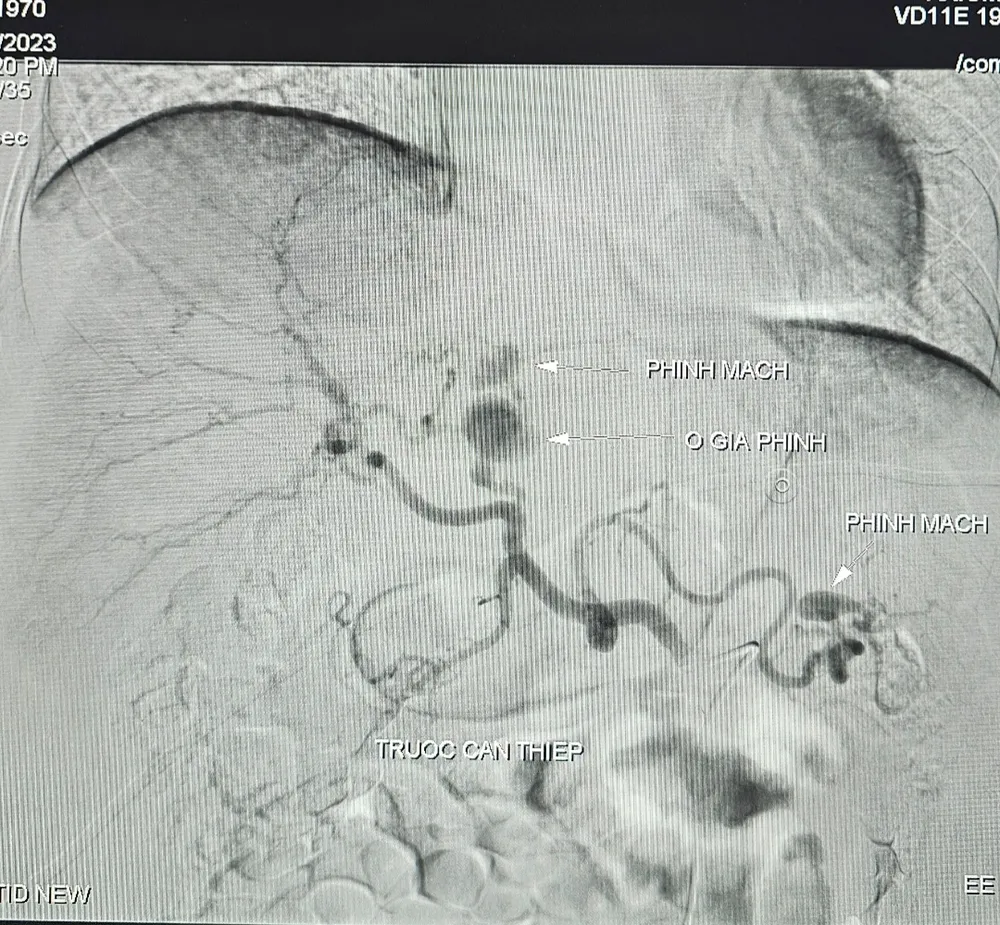

benh-hiem-gạp-truoc-can-thiep.jpg

Động mạch gan của bệnh nhân bị vỡ phình

Đến ngày, 10-12, bệnh nhân đột ngột đau bụng vùng thượng vị dữ dội, huyết áp thấp, mạch nhanh nhẹ, niêm nhợt, da xanh (dấu hiệu của mất máu cấp) nên nhanh chóng được hồi sức tích cực bù dịch, bù 06 đơn vị hồng cầu lắng. Kết quả chụp cắt lớp vi tính bụng có cản quang ghi nhận ổ giả phình được cấp máu từ động mạch gan trái kích thước to, tụ máu cạnh bao gan.

Bệnh nhân có chỉ định can thiệp chụp và nút động mạch điều trị cầm máu các tạng số xóa nền với chẩn đoán xuất huyết nội do vỡ phình động mạch gan trái, ghi nhận ổ giả phình động mạch gan trái, kích thước #15x22mm kèm phình động mạch gan.